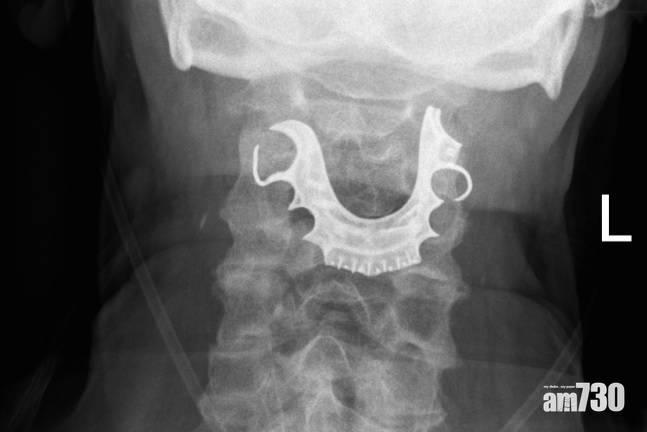

異物原來是一副假牙。(互聯網)

英國醫學期刊(British Medical Journal)前日刊出一宗罕有個案,一名72歲老翁早前為移除腹部硬塊而接受手術,但手術後喉嚨感到痛楚、咳出血、吞嚥困難,於是回到醫院求醫,醫生未有發現任何問題,只提供了抗生素、類固醇及嗽口水。老翁其後情況惡化,再度入院,醫生懷疑他嚴重肺炎並為他照X光,終發現一副假牙卡在他的喉嚨內,相信是8日前的手術時滑落至喉嚨。假牙附近的組織出現腫脹及水泡,需做手術取出。其後事主因動脈撕裂而不停出血,接受了另一次緊急手術,6周後才康復。撰寫報告的專家呼籲,醫生及醫護人員必須在手術前後確認病人是否有戴假牙。